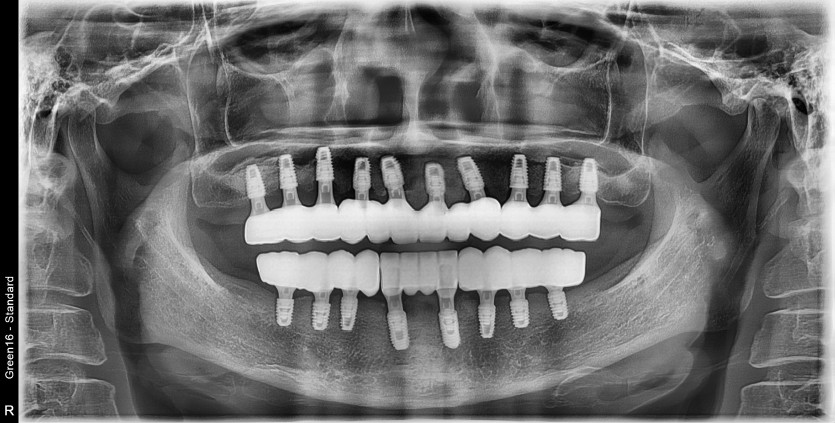

만 58세 전체 임플란트 증례입니다.

18개의 임플란트로 완성하였습니다.